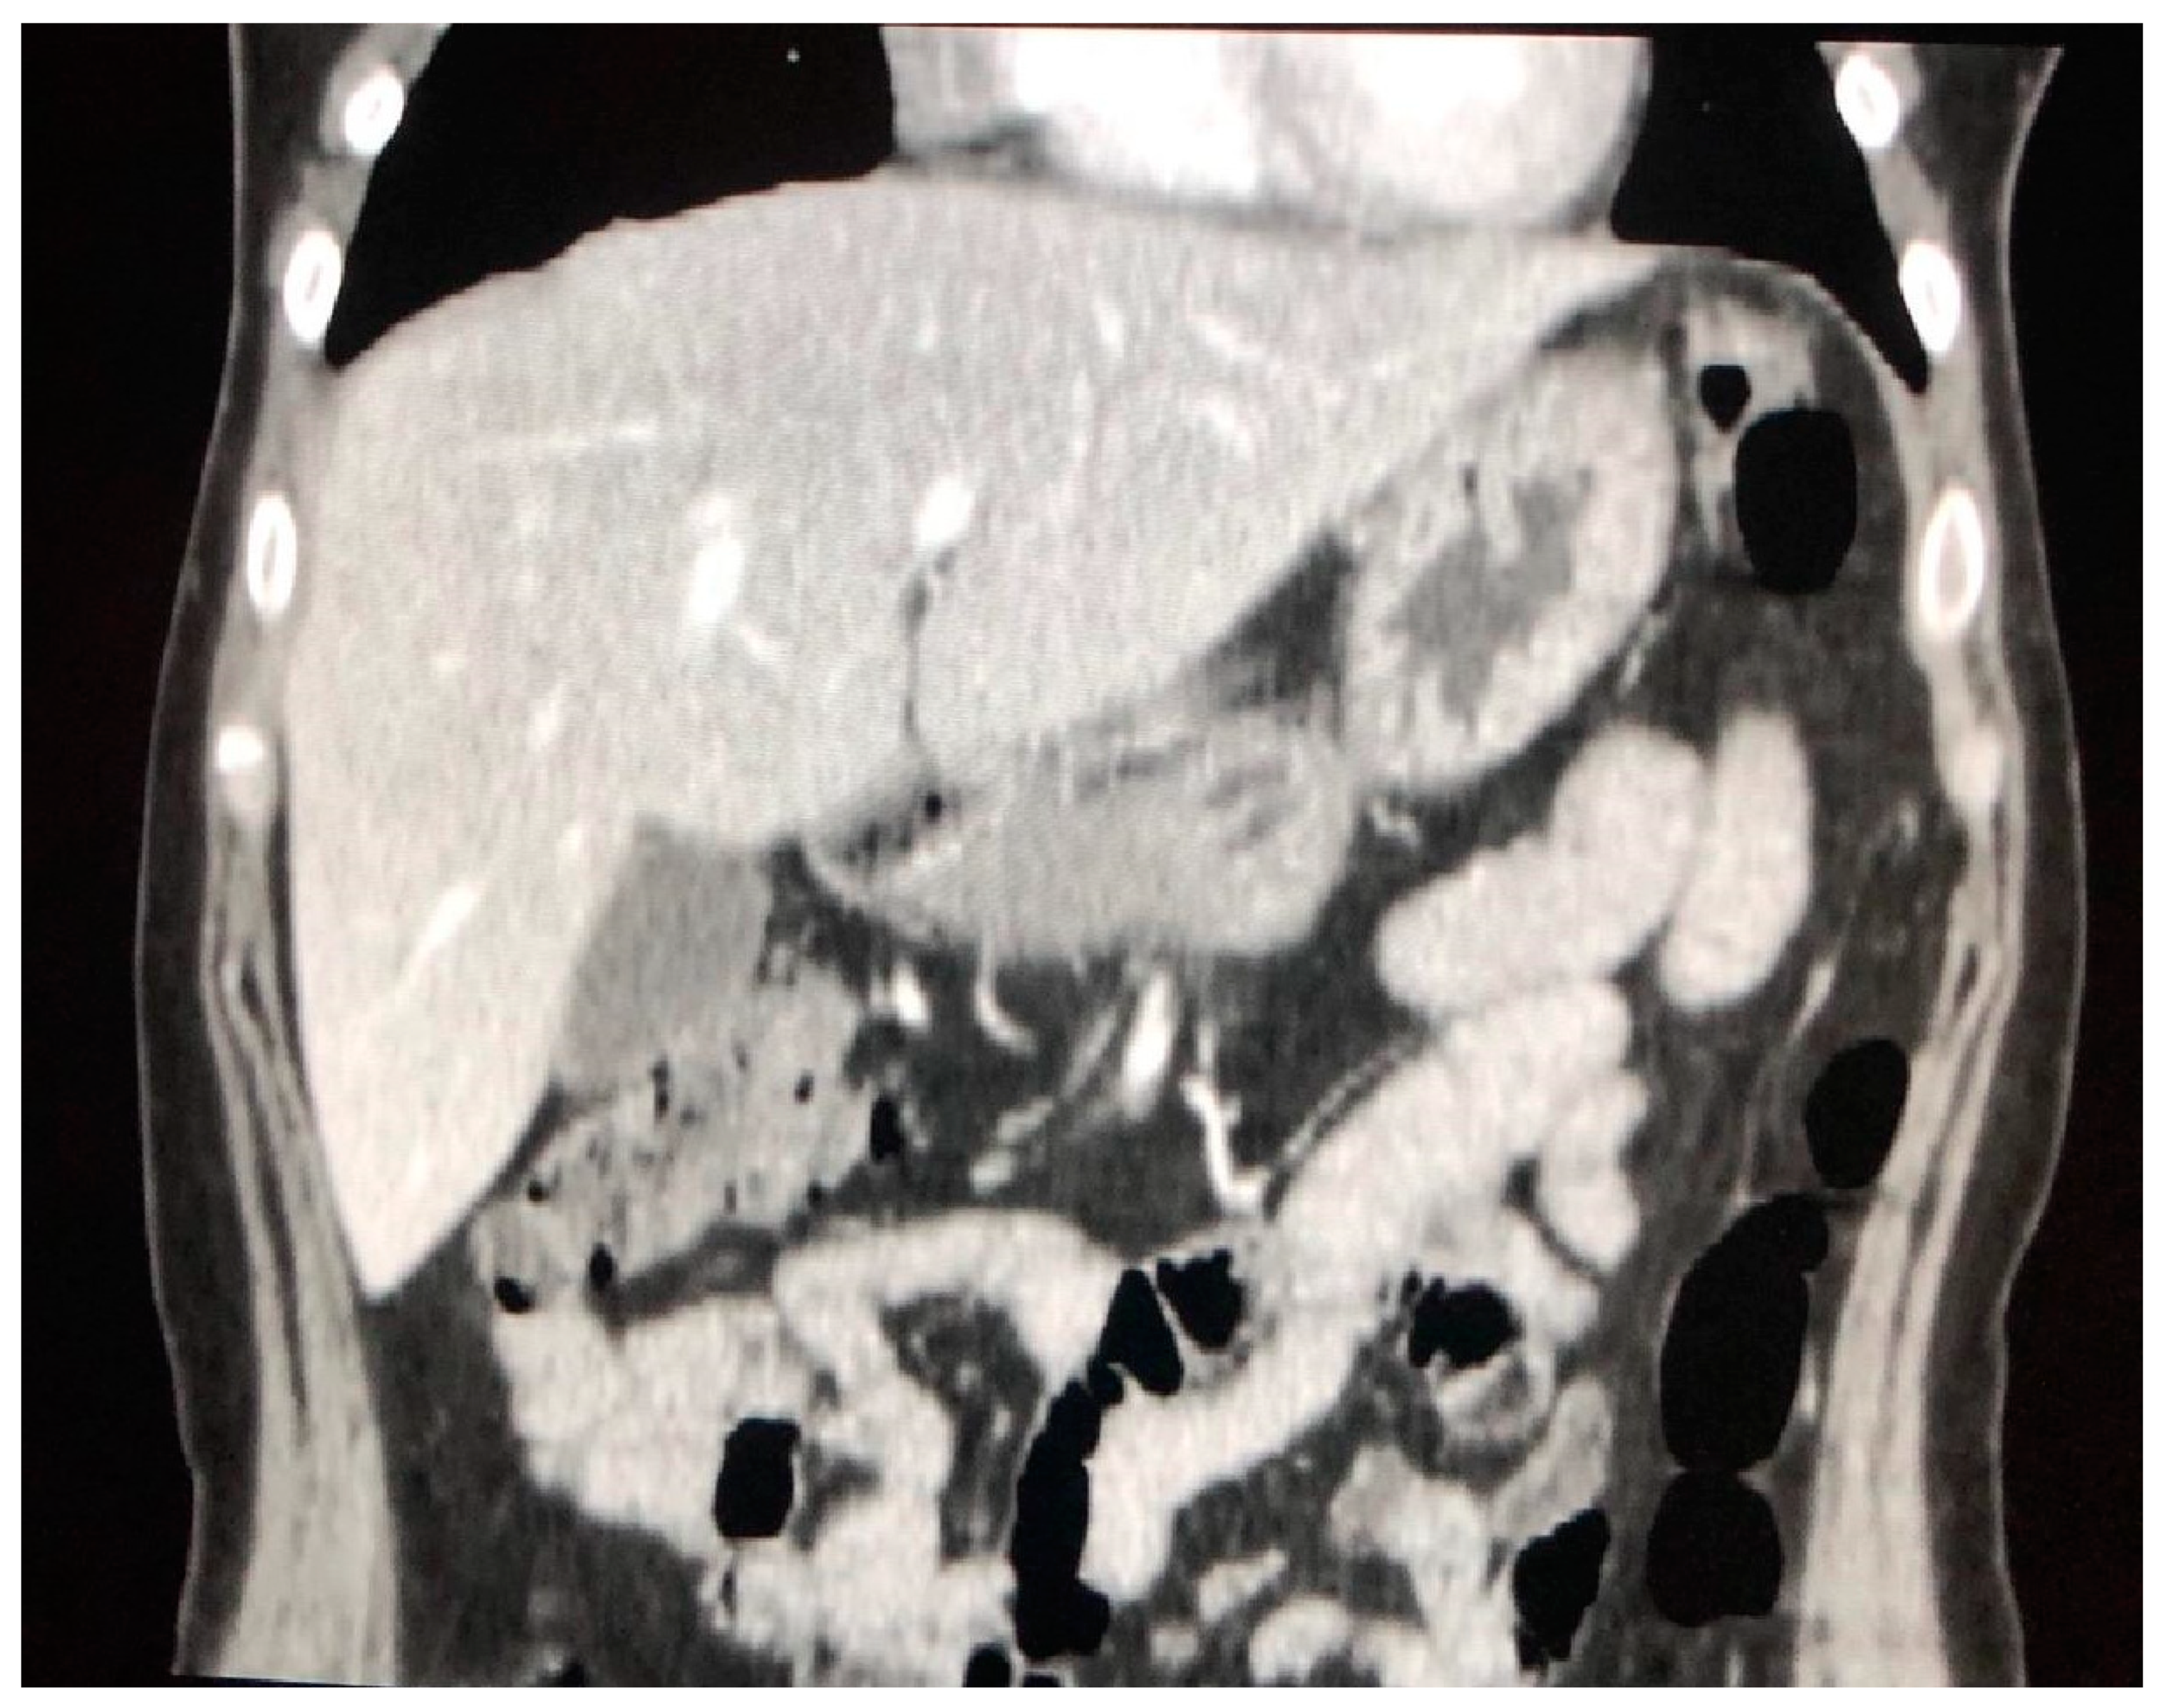

4.1. The Involvement of Liver, Spleen and Abdominal Lymph Nodes

- Palmucci, S.; Torrisi, S.; Caltabiano, D.C.; Puglisi, S.; Lentini, V.; Grassedonio, E.; Vindigni, V.; Reggio, E.; Giuliano, R.; Micali, G.; et al. Clinical and radiological features of extra-pulmonary sarcoidosis: A pictorial essay. Insights Into Imaging 2016, 7, 571–587. [Google Scholar] [CrossRef]

- Warshauer, D.M.; Lee, J.K.T. Imaging Manifestations of Abdominal Sarcoidosis. Am. J. Roentgenol. 2004, 182, 15–28. [Google Scholar] [CrossRef]

- Folz, S.J.; Johnson, C.D.; Swensen, S.J. Abdominal Manifestations of Sarcoidosis in CT Studies. J. Comput. Assist. Tomogr. 1995, 19, 573–579. [Google Scholar] [CrossRef] [PubMed]

- Warshauer, D.M.; Molina, P.L.; Hamman, S.M.; Koehler, R.E.; Paulson, E.K.; Bechtold, R.E.; Perlmutter, M.L.; Hiken, J.N.; Francis, I.R.; Cooper, C.J. Nodular sarcoidosis of the liver and spleen: Analysis of 32 cases. Radiology 1995, 195, 757–762. [Google Scholar] [CrossRef] [PubMed]